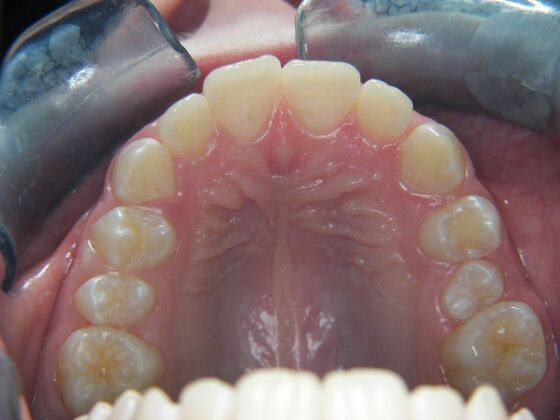

Patient is 9 years old and presents with 100% overbite and blocked out upper and lower lateral incisors. Both upper central incisors are palatally inclined causing a lack of space available for most anterior teeth. Advised her parents that she needs Phase I Interceptive Orthodontic treatment to provide room for all upper and lower front teeth. Phase I treatment was begun and finished, then began Phase II treatment shortly thereafter to finalize case. Removable retainer were fabricated for retention.